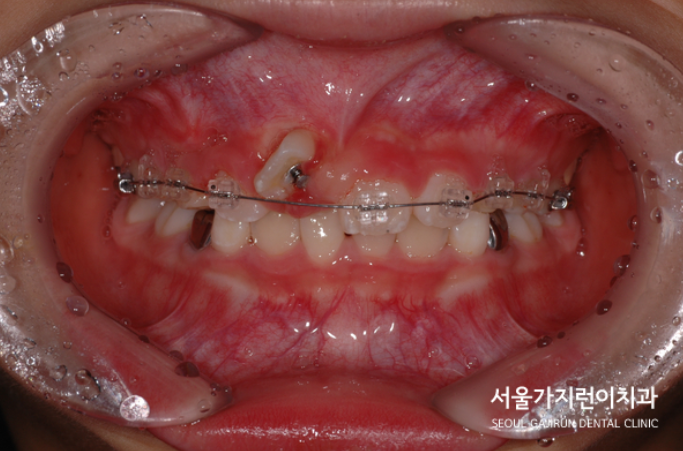

매복치의 견인을 위한 치아교정

위 사진을 보면 견인 방향을 고려해 치근의 흡수를 막고자 치아교정을 진행한 것을 확인할 수 있었습니다. 이때 주의할 점은 바로 뽑아내고 싶다고 무리하게 강한 힘으로 진행하게 된다면 문제가 될 수 있어 아주 약한 힘으로 견인치료를 했는데요. 치료를 시작한지 14개월이 지난 결과를 확인해볼까요?